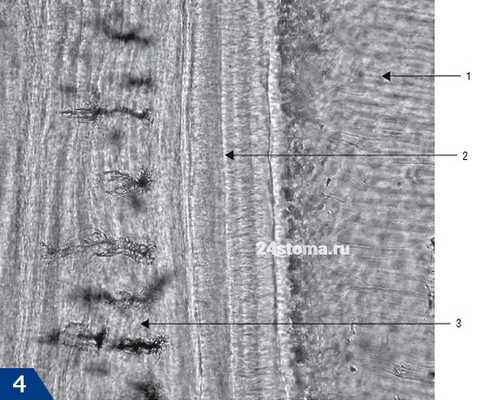

Линии Эбнера (ростовые линии, контурные линии) на участках со сниженной минерализацией, отражающей фазы покоя одонтобластов в период развития дентина. Они проходят в околопульпарном дентине параллельно границе эмаль-дентин или же границе дентин-пульпа.

Линии Оуэна - более гипоминерализованные ростовые линии встречают ся чаще. Они отражают общие заболевания в детском возрасте, влияющиеся на процессы с пониженной минерализацией твердых тканей зубов.

Линии новорожденных в молочных зубах и коронковой области первых постоянных моляров - особая форма ростовых линий, возникших вслед ствие гипоминерализации. Она соот ветствует более длительной фазе по коя одонтобластов (==15 дней). Интерглобулярный дентин. Дентинные канальцы не имеют в этой области перитубулярного дентина. Возможно, речь идет об образовании нерегулярных минерализованных участков дентина. Интерглобулярный дентин - основное вещество дентина, располо женное между дентинными слоями.